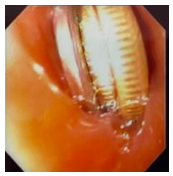

A imagem abaixo, que foi capturada ao nível do terço superior do esôfago durante exame endoscópico,

se refere à endoscopia de um paciente de 4 anos, assintomático, que diz ter engolido uma moeda: